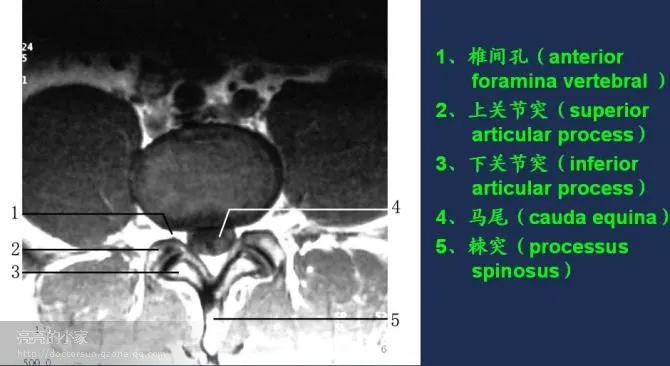

收藏!全身MRI解剖图谱,医生必备